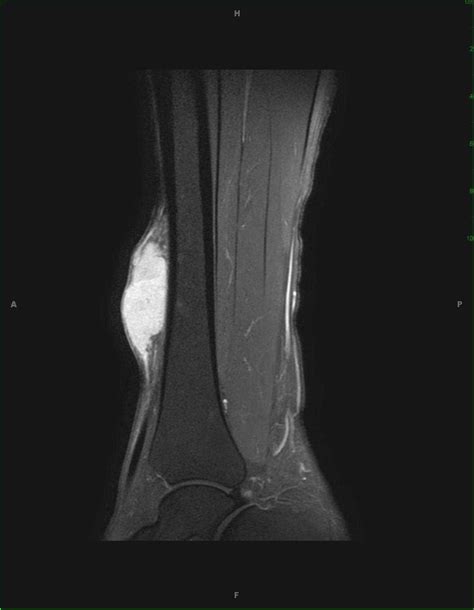

MRI or CT Scan To determine the size, location, and involvement of the tumor in surrounding structures.

These tumors can develop almost anywhere in the body, though they most frequently arise in the limbs, trunk, or retroperitoneum (the area behind the abdominal cavity). Because they often present as painless lumps that grow slowly, patients may not notice them until they become large enough to cause physical discomfort or restrict movement by pressing on surrounding tissues.

At its core, Spindle Cell Sarcoma is a classification of soft tissue sarcoma characterized by malignant cells that appear elongated, or "spindle-shaped," when viewed through a microscope. It is not a single, monolithic disease; rather, it is a morphological diagnosis that can encompass several distinct subtypes of sarcoma. Because these cells lack specific markers, they can be difficult to distinguish from other types of cancer, necessitating advanced diagnostic techniques such as immunohistochemistry and genetic testing.